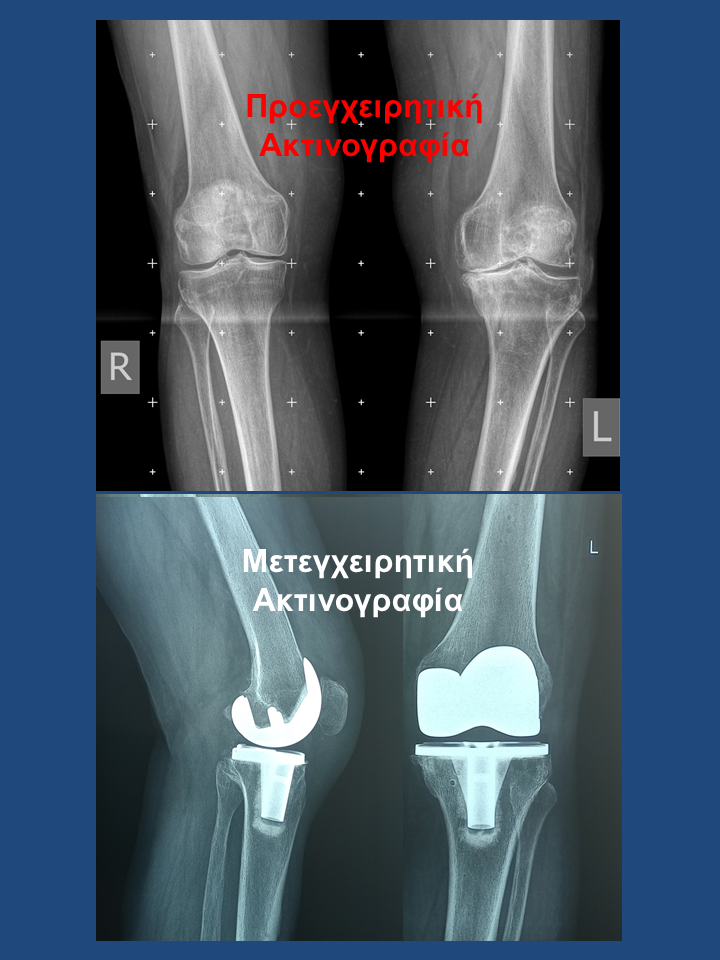

Ρομποτική αρθροπλαστική και στα 2 γόνατα στο ίδιο χειρουργείο

Ασθενής 75 χρονών με οστεοαρθρίτιδα και στα 2 γόνατα. Είχε επιδεινούμενο άλγος τα τελευταία 2 χρόνια που την δυσκόλευε στη βάδιση και την αφυπνούσε το βράδυ. Υπεβλήθη σε ρομποτική αρθροπλαστική και στα 2 γόνατα την ίδια ημέρα. Χρησιμοποιήθηκε η τεχνική διατήρησης οστού όπου αφαιρέθηκαν λιγότερα χιλιοστά οστού. Ο άξονας στο αριστερό γόνατο από 100 αποκαταστάθηκε στις 00 και ομοίως στο δεξί. Η κάμψη στο αριστερό αποκαταστάθηκε στις 1160 . Η ασθενής βαδίζει πλέον χωρίς καμία ενόχληση.